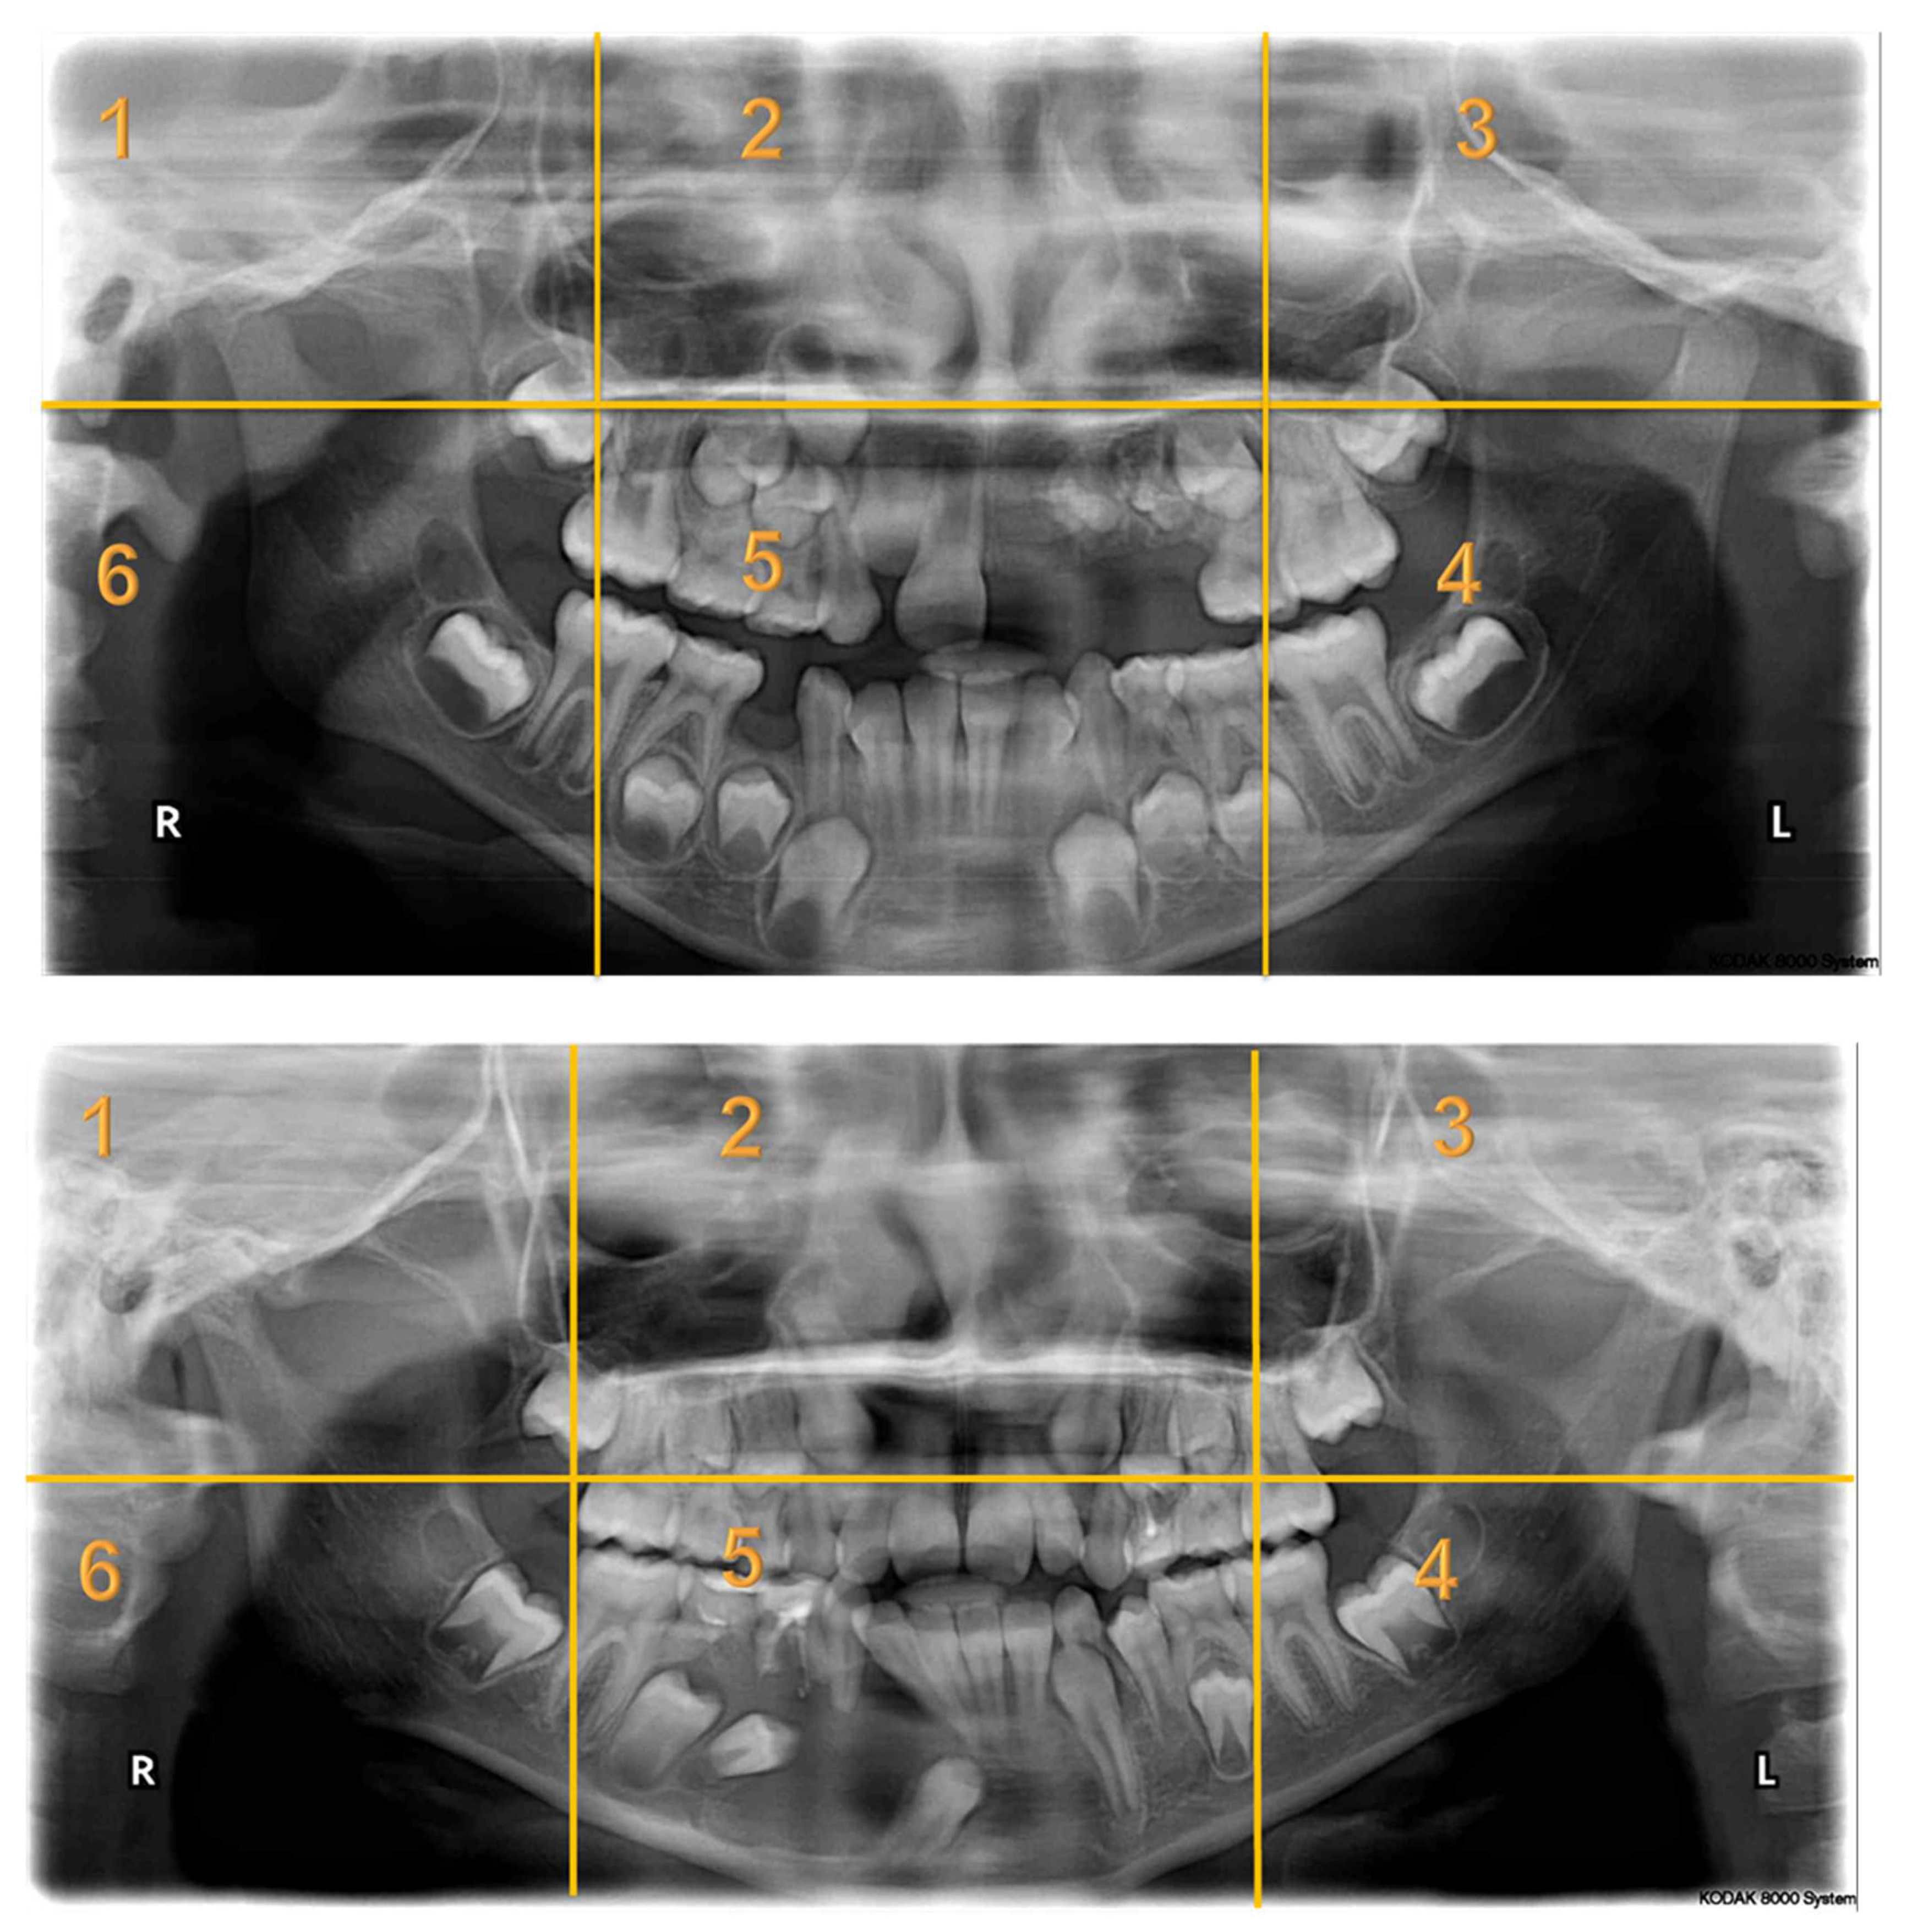

Seven panoramic radiographs (Appendix A) of pediatric dental patients aged between 6 and 16 years of age were selected from the electronic health system of KAUDH, based on their quality. Case selection mandated the presence of at least one bony lesion. A panel of experts from KAUDH, including three pediatric dentists and an oral radiologist, reviewed the selected cases to ensure that the radiographs were of good quality. All the images used in the study underwent no manipulation. The type of lesion was recorded for each patient and confirmed by their dental records. All identifying data were removed and a de-identified serial number was assigned to each case. The panoramic radiographs in this study presented a wide variety of abnormalities that included deviated nasal septum and enlarged nasal conchae; fibrous dysplasia; regional odontodysplasia or ghost teeth; dentigerous cysts; odontogenic keratocysts; enlarged dental follicle; missing, impacted, and rudimentary teeth; dilacerated roots; retained primary teeth; and periapical radiolucencies.

Appendix A. Radiographs Included in the Study